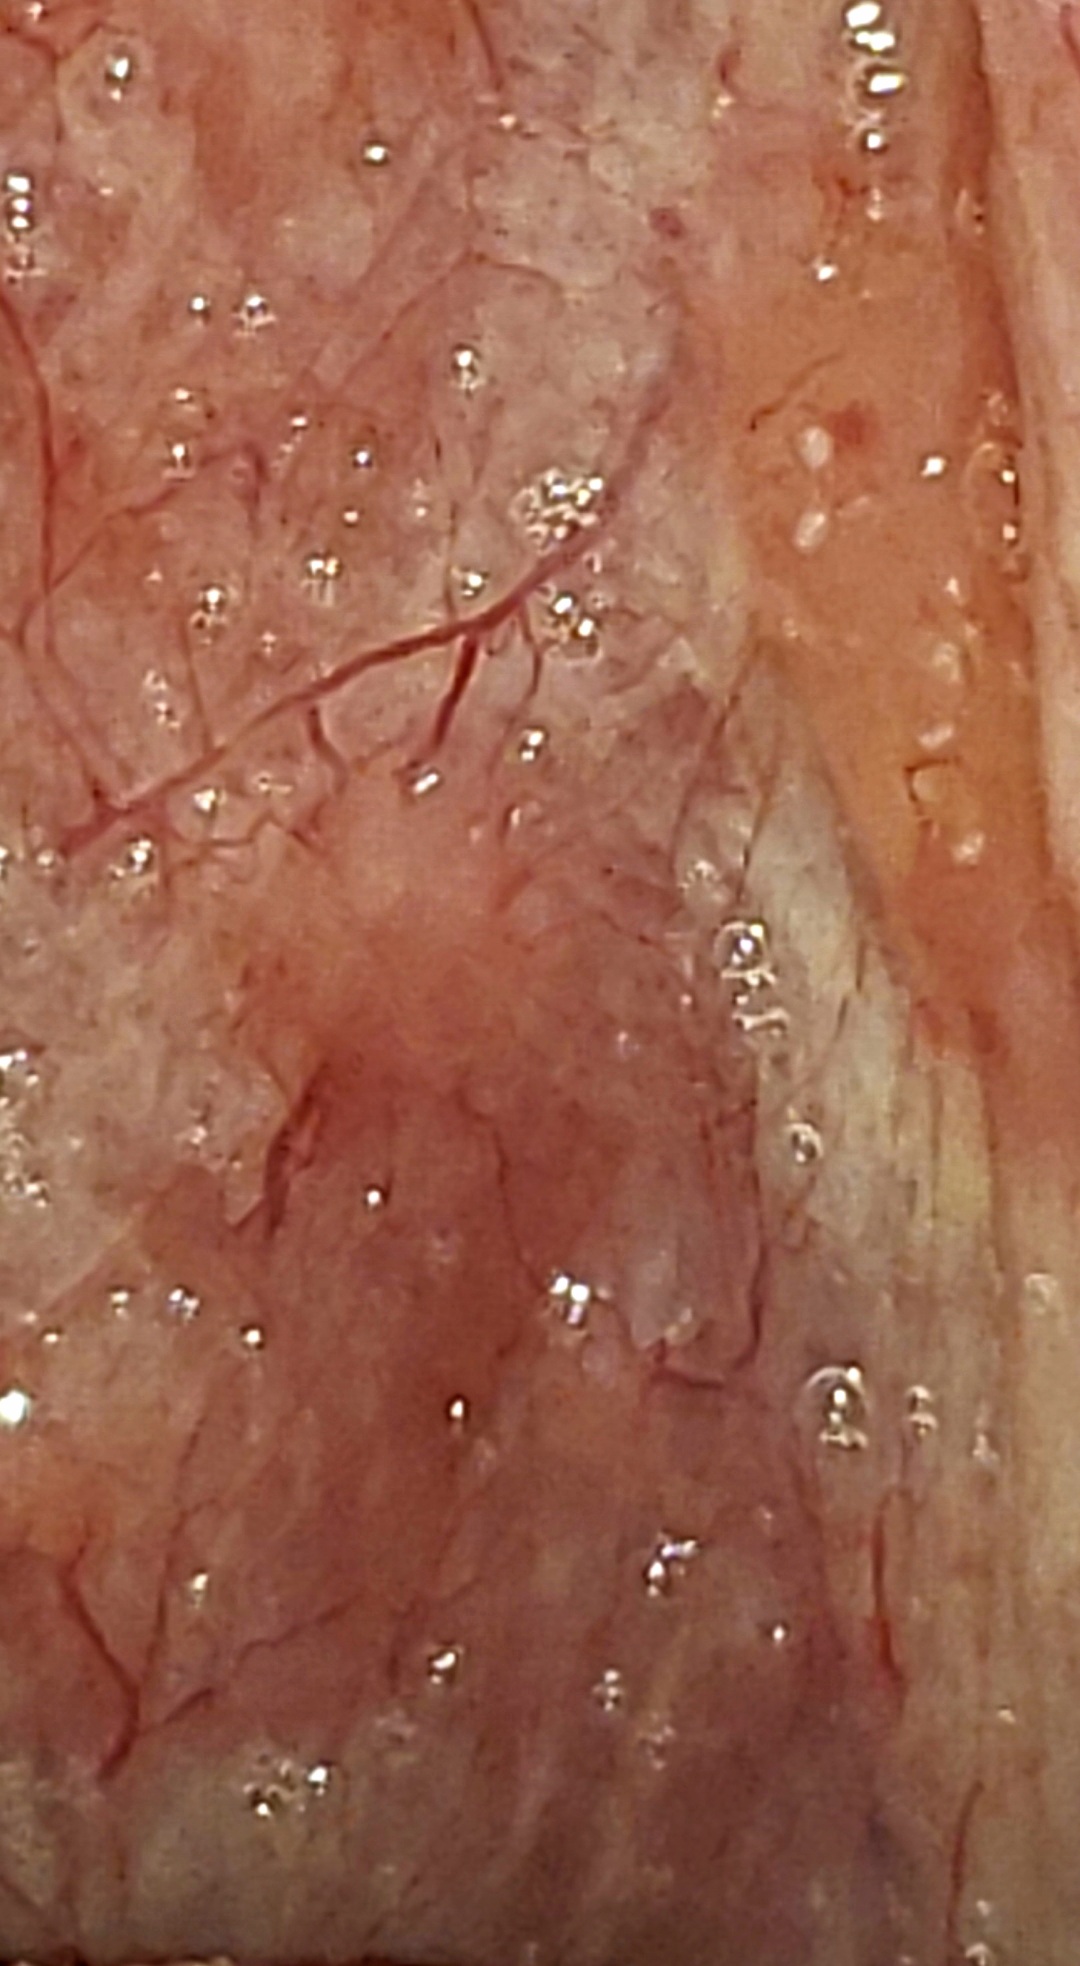

Does anyone know what these are ? I need help please 12 years of this and I'm pretty sure I'm dieing. My hair moves by itself ,my gallbladder removed ,my liver is failing. I have a suspicious feeling these have something to do with it. Had Candidiasis when my first was born and mrsa. Dont know if it's got something To do with it or not. They're also turning up in my stool attacked to what looks to be skin idk must be my stomach lining or skin from walls of intestin idk

heres more pictures

I'm also sorry that you're going through this and for so long. I firmly believe my symptoms are from a parasitic infection. I have several things going on because of it, but your post caught my eye b/c your pics looked exactly like some of mine. I've been to many doctors who either don't know or continue to tell me all looks fine. Of course, I know all is not fine. My scariest symptom is the dizziness that feels like I'm bobbing up & down on a boat. That started over a year ago & is 24 hrs a day 7 days a week. Recently, I started seeing really strange things where my tonsils are & the back of my throat. I'll post a pic. Went to ENT doctor who told me my throat looked "perfectly normal" and thar I should stop looking at it!! Talk about being pissed, I just raised my eyebrows & walked out. Doctors do not want to even consider parasitic or fungal infections. And, if the rare one does, they have no clue how to diagnose. Every other country sees it as a normal part of medical practice except the U.S.A. I believe there are many suffering because of this & research is showing more & more that many other diseases are caused by parasites. It's incredibly discouraging. If I happen to learn anything helpful I will certainly let you know. I think my issue may be strongyloides & their also in my hair follicles because my hair will move also (I think you had posted that too). I have videos & doctors still look at me like I'm crazy. I am so sorry for your suffering & will pray for a break thru for you.